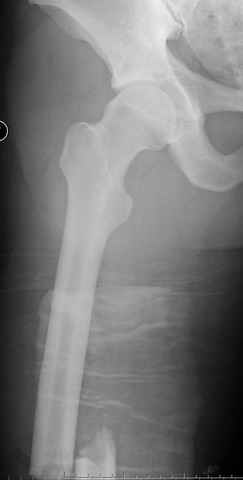

больному 42, автоавария, политравма, открытая черепномозговая травма, безсознании, открытый перелом бедра, размозжение мягких тканей, дефект кожи на передней поверхности бедра около 13 см2 от ожога, компартмент синдром.

По поводу открытого перелома больной ургентно взят на ретроградное интрамедулярное штифтование, после рутинного дебрайдмента и фасциотомии на бедре и на голени.

перелом бедра

интраоперационные

постоперационные